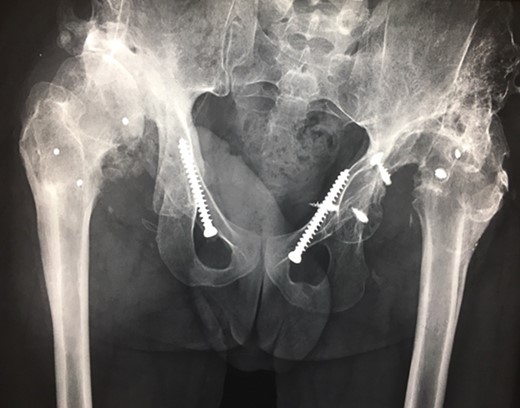

(A + B): (2019) (A) x ray of the pelvis after a 10 year follow up. The right head further migrated und subluxated and femoral head necrosis is visible, new bone formation at the ileum stabilizing the joint. At the left side high dislocation of the hip with fully necrosis of the head and ankylosis of the hip joint. (B) MRI showing hip effusion around the joint which is painless.

At this stage patient’s walking ability was already limited due to muscle weakness and rubbing in the hip joints, so we recommended no further walking and weight bearing. Further follow-up at 5 years (Fig. 7) and 10 years (Fig. 8A) until today showed radiologically complete absorption of the left femoral head and the right hip continuously moving cranially creating a false acetabulum and a flattened femoral head. At final follow up the patient was in a wheel chair but able to bend both hips up to 110 degrees without noticeable pain, he could stand up with help for a short time and showed a massive Charcot joint with effusion (Fig. 8B) of the right hip without further clinical implications.